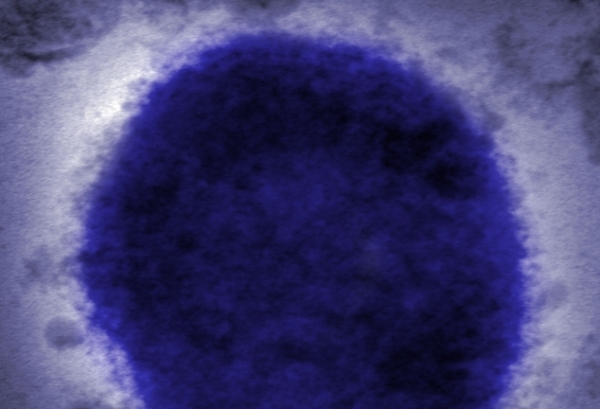

وعادة ما يظهر الفيروس، وهو أحد أقارب الجدري، كمرض خفيف لا يستمر أكثر من بضعة أسابيع.

وفي حين أن أعراض كلا المرضين متشابهة، إلا أن علامات جدري القرود تكون أكثر اعتدالا بشكل عام من أعراض الجدري.

وعلاوة على ذلك، فإن تورم الغدد الليمفاوية هو سمة بارزة لجدري القرود، وهو أقل شيوعا مع الجدري. ولا تنتقل العدوى الفيروسية النادرة، التي تقتل ما يصل إلى واحد من كل 10 أشخاص في إفريقيا، بسهولة بين البشر.

ويمكن أن يسبب الحمى والصداع والطفح الجلدي، والتي قد تسبب بثورا مماثلة لتلك التي تظهر مع انتشار جدري الماء.